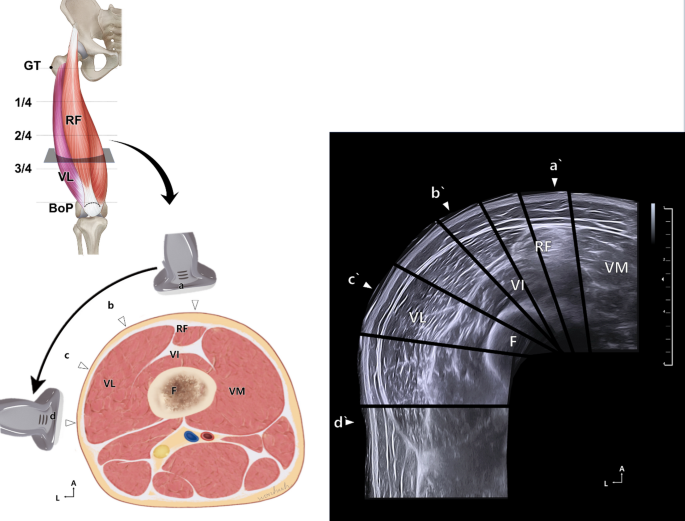

During the scanning process, the ultrasonography transducer was placed transversely to differentiate between the vastus intermedius and VL (Fig. 1). Subsequently, the transducer was shifted towards the VL insertion site to observe whether the muscle gradually narrowed and became thinner. This step confirmed the precise identification of the VL using ultrasonography. Subsequently, both the median and lateral lines of the thigh were trisected, and the injection point was designated as the 2/3 lateral line intersecting the midpoint of the VL (GT to BoP). The transducer was placed close to the puncture site, and the needle was advanced under direct echographic visualization using a real-time technique in the in-plane method, moving transversely.

Ultrasonography scanning method for ultrasound-guided injections and corresponding cross-sectional images. Three transverse lines (1/4, 2/4, and 3/4) divided the vastus lateralis (VL) into four zones. The black transparent plane in the upper left illustration represents the scanning site. Scanning was performed from points a to d in the anterior-to-lateral direction to visualize the entire VL muscle, with each site corresponding to a′–d′ in the ultrasonography image. GT, greater trochanter; BoP, base of patella; RF, rectus femoris muscle; VI, vastus intermedius; VM, vastus medialis; F, femur; A, anterior; L, lateral.